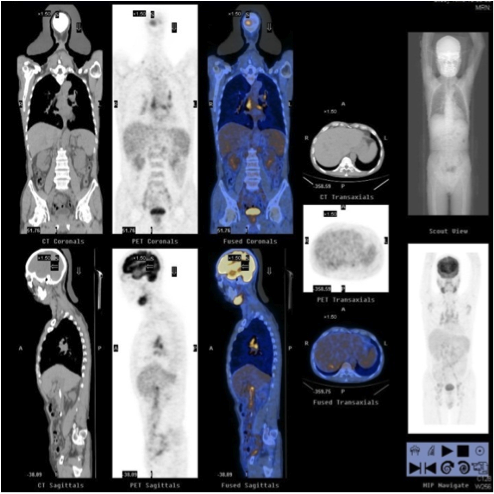

Three months later, patient was admitted for obstructive jaundice. His liver function was deranged with bilirubin 132, ALP 386, ALT 346. Ultrasound abdomen showed dilated common bile duct. Patient had the endoscopic retrograde cholangiopancreatography (ERCP) done and it found smooth stricture at common hepatic duct close to hila. Ampulla biopsy showed benign small bowel mucosa with focal neutrophilic intraepithelial infiltration and ulceration. There was no evidence of malignancy. Contrast CT abdomen and pelvis was also performed. It revealed again dilated common bile duct. Also there were multiple enlarged portal, mesenteric, retroperitoneal and groin lymph nodes. He had a 1cm cystic lesion at the tail of pancreas. In view of suspected malignancy, positron emission tomography (PET) was done (Fig 3A, 3B). There was no hypermetabolic lesion in liver and pancreas, but multiple hypermetebolic lymph nodes were found in head, neck, thorax, abdomen and pelvis. Also the bilateral submandibular glands showed intense FDG uptake with SUV max 7.5.

Patient was treated with prednisolone 30mg daily, and then had the prednisolone tailing down to 10mg daily with azathioprine 50mg daily added. The PET scan 3 months after treatment showed significant metabolic improvement (Fig 5). CT thorax also showed decreased tree-in-bud opacities and septal thickening.